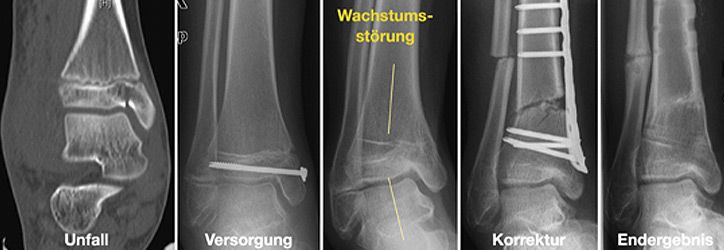

Für die Behandlung von Knochenbrüchen im Kindesalter sind genaue Kenntnisse des Wachstums nötig. Knochenbrüche können das Wachstum hemmen, überschießen oder fehlleiten. Andererseits können Fehlstellungen in bestimmten Grenzen alleine durch Wachstum korrigieren werden. Somit sind für eine Therapieentscheidung die Faktoren Patientenalter, Fehlstellungsausmaß und Korrekturpotenz von größter Bedeutung.

- Operative Korrekturen von fehlverheilten Knochenbrüchen

Andere Verfahren der operativen Frakturversorgung im Kindesalter sind die Kirschner-Draht-Osteosynthese, die Verschraubung, der Fixateur und die Plattenosteosynthese. Metallentfernungen werden ambulant durchgeführt, Nachuntersuchungen zum Ausschluss etwaiger Wachstumsstörungen erfolgen in unserer Frakturensprechstunde.

Korrekturoperation

Nur selten treten Wachstumsstörungen oder Verheilungen in Fehlstellung auf. Um dennoch eine volle Belastung und uneingeschränkte Beweglichkeit zu gewährleisten, führen wir entsprechende Korrekturoperationen durch.